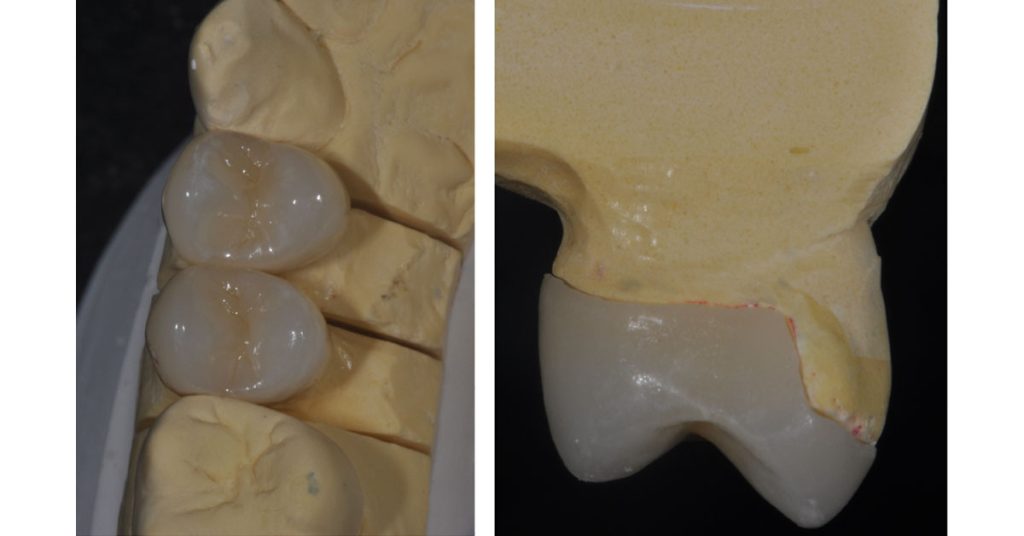

The photos above show the pre-treatment tooth and the required cuspal coverage due to enamel erosion. The diagnostic wax-up provides a preview of the desired outcome. Note the cuspal height changes that are to be incorporated into the final restoration. This is a key observation! Ceramic restoration failures occur due to inadequate reduction related to final-outcome contours.

Diagram 2 is of the diagnostic wax-up, or the “proposed outcome” contour of the final restoration. The restoration proposal has integrated significant changes in occlusal anatomy and cup height. These changes must be considered in the tooth preparation to provide adequate thickness for the partial coverage ceramic onlay.

The following photos show the final ceramic onlays for the patient’s #12 and #13 teeth: